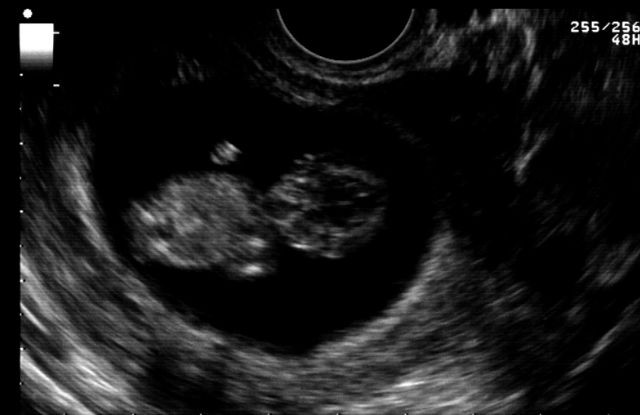

10. Hafta Anne Karnı Bebek Ultrason Görüntüleri